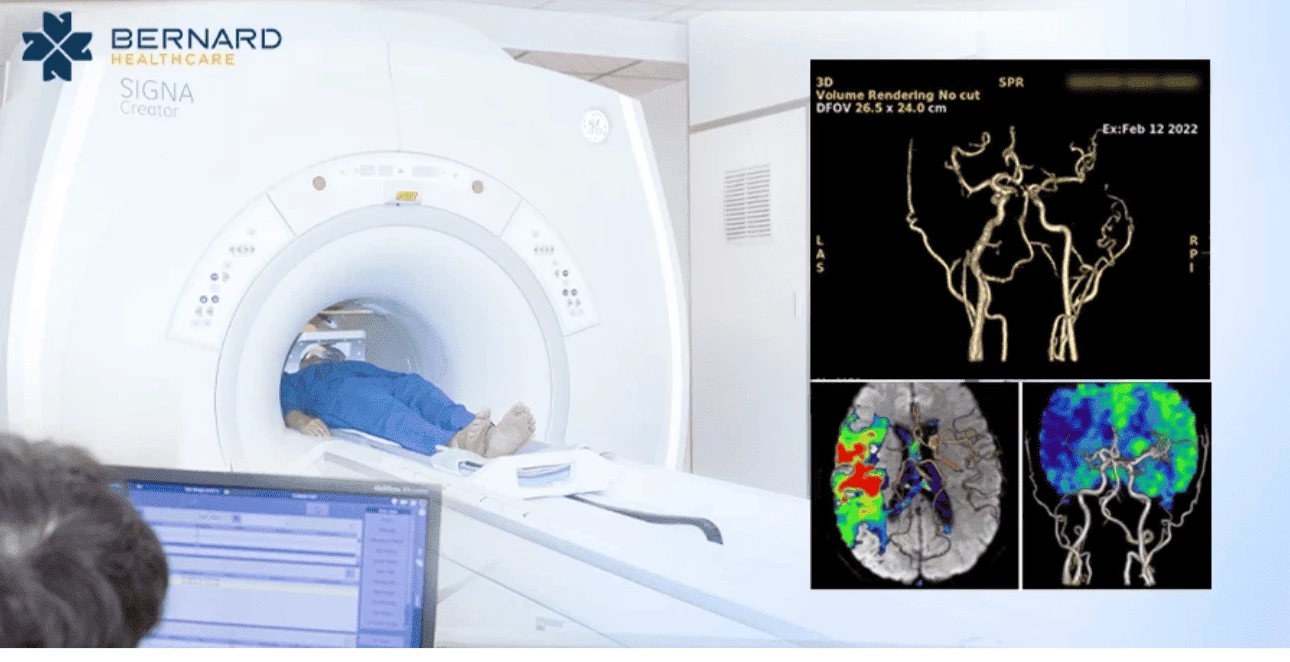

Hệ thống MRI (chụp cộng hưởng từ) 1.5 Tesla SIGNA Creator phiên bản đầy đủ (full option) được tích hợp trí tuệ nhân tạo (AI)

Hệ thống MRI tại Bernard Healthcare có các phần mềm hỗ trợ thăm khám chuyên sâu cho thần kinh, bộ COIL chuyên biệt cho nhũ và các ứng dụng MRI khuếch tán xung toàn thân (MRI WB-DWI) cho tầm soát ung thư toàn thân.

MRI với công nghệ dựng hình chuyên sâu AI PACs giúp các bác sĩ Bernard khảo sát mạch máu não, dựng hình 3D mạch máu não và đánh giá tưới máu não, từ đó truy tìm ra các yếu tố nguy cơ thầm lặng gây đột quỵ

MRI với COIL nhũ chuyên biệt không gây đau, không chèn ép ngực, không dùng tia X chuyên biệt trong chẩn đoán và đánh giá giai đoạn ung thư vú, đặc biệt an toàn cho phụ nữ đặt túi ngực. Quá trình tầm soát diễn ra êm ái, thuận tiện mà vẫn có thể phát hiện sớm các bất thường chỉ vài milimet hoặc ẩn sâu sau lớp túi ngực.